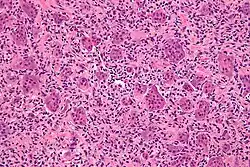

| Micrograph of a giant-cell tumor of bone showing the characteristic giant cells, H&E stain | |

Giant-cell tumor of the bone (GCTOB) is a relatively uncommon bone tumor characterized by the presence of multinucleated giant cells (osteoclast-like cells). Malignancy in giant-cell tumor is uncommon and occurs in about 2% of all cases. However, if malignant degeneration does occur, it is likely to metastasize to the lungs. Giant-cell tumors are normally benign,[1] with unpredictable behavior.[2]

It is a heterogeneous tumor composed of different cell populations. The giant-cell tumour stromal cells (GCTSC) constitute the neoplastic cells,[3] which are from a mesenchymal stem cell origin and are classified based on expression of osteoblast cell markers such as alkaline phosphatase and osteocalcin. In contrast, the mononuclear osteoclast precursor cells giving rise to multinucleated giant cells (MNGC) are secondarily recruited and comprise the non-neoplastic cell population. They are derived from an hematopoietic monocyte/ macrophage lineage determined primarily by expression of CD68, a marker for monocytic precursor cells.[4][5][6] In most patients, the tumors are slow to develop, but may recur locally in as many as 50% of cases.

The diagnosis of giant-cell tumors is based on biopsy findings. The key histomorphologic feature is, as the name of the entity suggests, (multinucleated) giant cells with up to a hundred nuclei that have prominent nucleoli. Surrounding mononuclear and small multinucleated cells have nuclei similar to those in the giant cells; this distinguishes the lesion from other osteogenic lesions which commonly have (benign) osteoclast-type giant cells. Soap-bubble appearance is a characteristic feature.